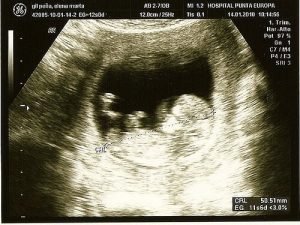

초음파

문제를 감지하고 아기의 첫 사진을 얻는 데 유용한 매우 흔한 절차이다. 이 절차에서 부부는 아이의 성을 알게된다. 또한 심장 결함과 염색체 변형과 같은 이상을 감지한다.

2단계 초음파는 태아가 갖고 있을지도 모르는 결함 가능성을 자세히 살펴보기 위해서 추천하는 검사이다. 선별검사에서 비정상 가능성이 보일 때 이 검사를 받을 것을 권한다.

파동을 이용하여 영상을 만들어내는 기구를 통해서 영상을 얻고, 수술을 하지 않는 기술이다. 파동은 아이에게 해가 되지 않고 자궁 내에서 일어나는 일을 관찰할 수 있게 해준다.